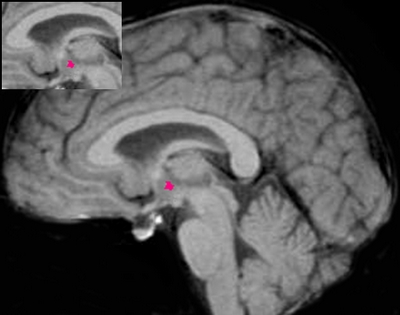

国内利用功能磁共振来进行肥胖机制的研究尚不多见。卫生部北京医院放射科副主任陈敏教授多年来一直从事磁共振成像的临床研究,他率先应用功能性磁共振(fMRI)观察不同体重者下丘脑对口服葡萄糖耐量试验的反应。研究观察到,不同体重者口服葡萄糖后在下丘脑部位均出现一过性的抑制反应,但肥胖者抑制反应出现的时间较正常体重者明显延迟;抑制反应的强度明显低于正常体重者;抑制反应恢复时间也明显迟于正常体重者。从而可以推论不同体重者下丘脑对糖负荷的中枢反应有所不同,肥胖者下丘脑对糖刺激反应的敏感性有所降低。

红色记号是功能性磁共振显示的肥胖者口服葡萄糖后下丘脑功能出现抑制反应的区域。